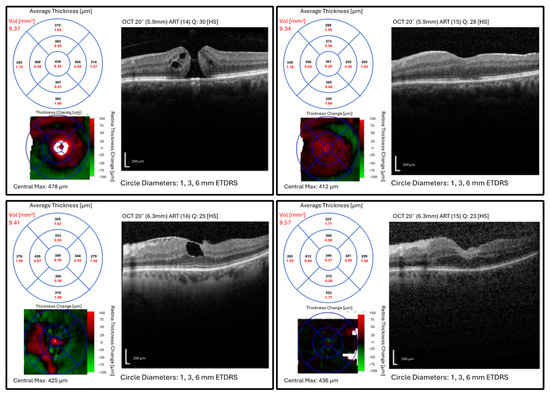

Figure 4.

Macular optical coherence tomography images, average thickness and volume within ETDRS grid (1, 3, and 6 mm), and thickness change map of patients with a full-thickness macular hole before (top left) and after (top right) surgery and lamellar macular hole before (bottom left) and after (bottom right) surgery. Abbrev.: ETDRS, Early Treatment Diabetic Retinopathy Study; Vol, volume.